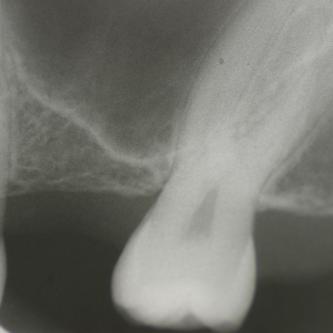

Exemple 14: Il est prévu de mettre un implant entre la molaire et prémolaire, mais le sinus se trouve à moins de 4 mm de la surface. Il faut donc relever le sinus avec une greffe d'os

Exemple 14: Un petit puits d'accès est créé afin d'atteindre le sinus, notez la membrane sinusienne.